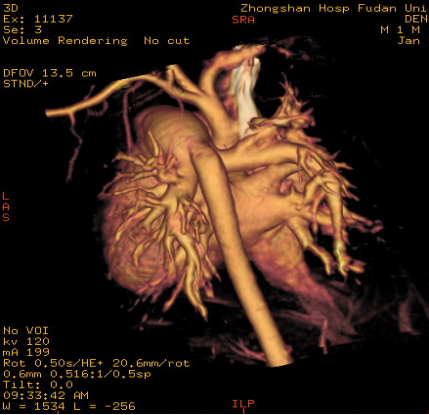

4、多排螺旋CT三维成像 (Multi - slice CT Three - dimensioned Angiography ):

大血管形态、 冠状动脉形态-依靠心率

主动脉弓缩窄伴弓部及降部发育不良 主动脉弓离断:升主动脉与降主动脉不连续,

降主动脉通过粗大动脉导管供血